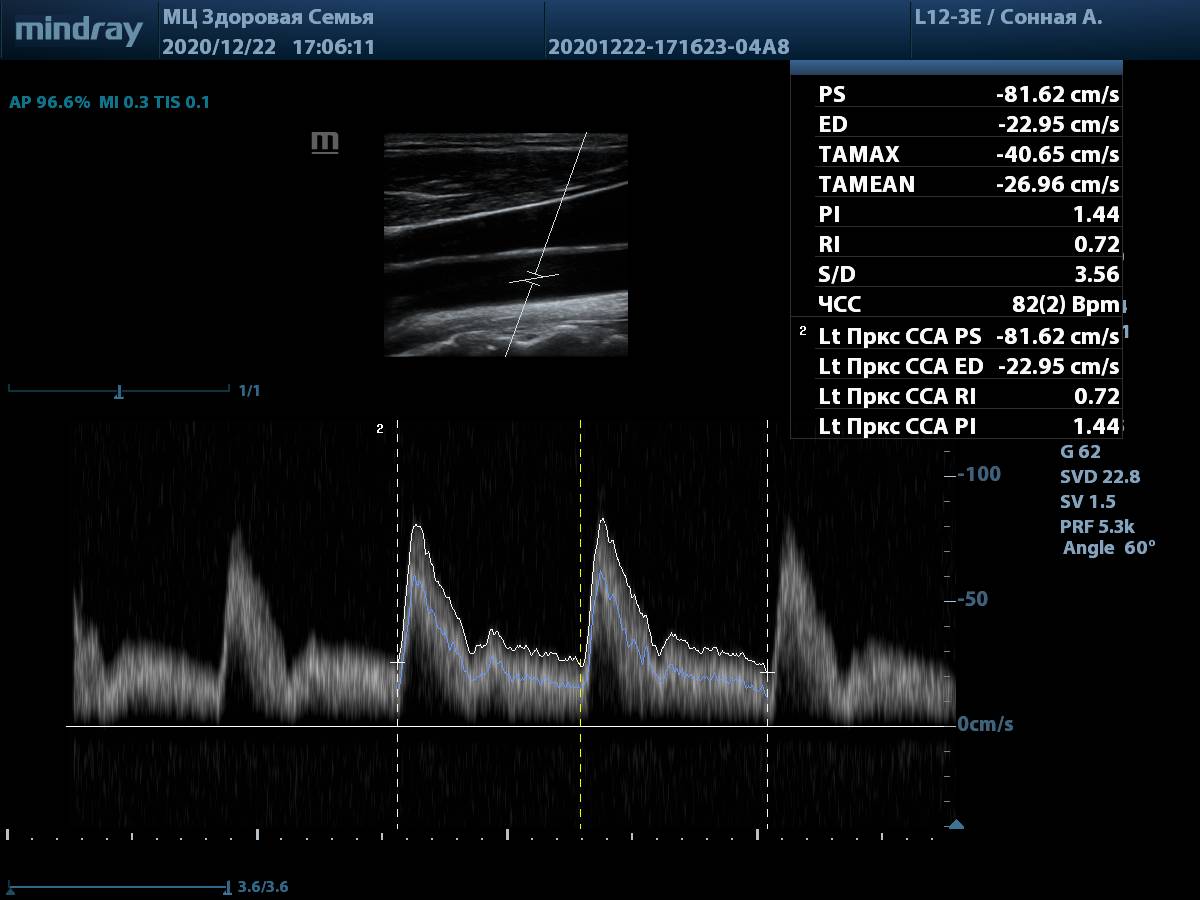

9. Общая сонная артерия, PW-допплер. Автоматическая трассировка игнорирует мелкие артефакты, четко повторяя спектр, а также использует несколько комплексов для снижения погрешности. Для отправки результата в отчет достаточно выбрать параметр в меню измерений.